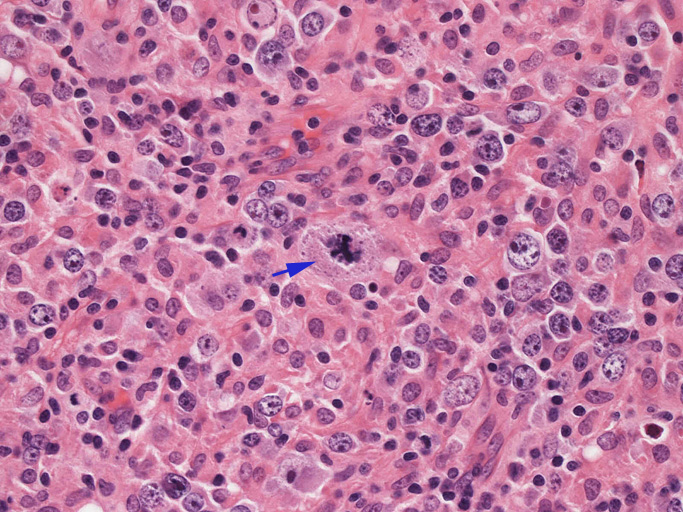

結節構造内では, 好酸性細胞質をもつ組織球の増生を背景に大型異型細胞が散在性または集蔟して増殖している。被膜下にも線維化組織内にbizzarreな大型細胞が認められる。リンパ球は小型リンパ球が大型異型細胞を含む組織球性の結節辺縁に存在する。大型細胞は, centroblastic cellが多く, その他 Hodgkin cell-like cell, RS細胞様巨細胞, 腎臓型の核をもった細胞, 多型核の細胞など多彩な形態を示す。異型核分裂像をふくむ核分裂像が多い。

大型異型細胞の形態

| Hodgkin cell-like | centroblastic | centroblastic | multinucleic |

| anaplastic large | kidney-shaped | mirror image | atypical mitosis |